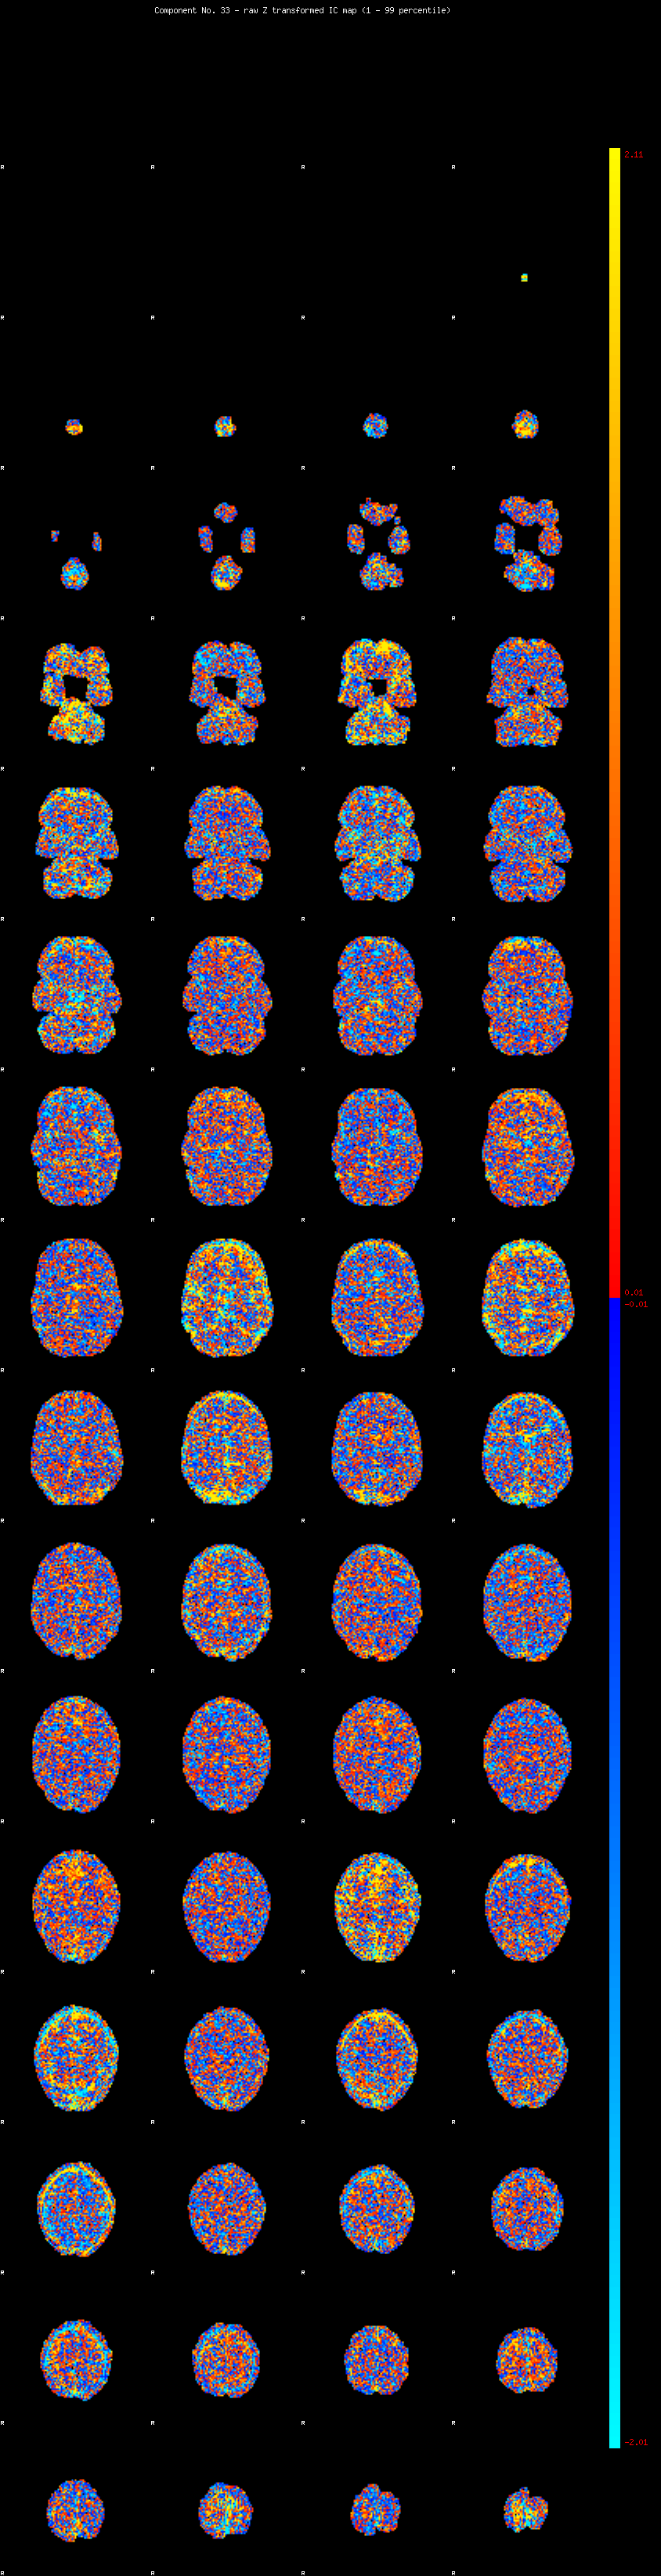

IC_33 Mixture Model fit

Means : -0.000000 2.732854 -2.410972

Vars : 1.000000 2.850242 1.787477

Prop. : 0.922077 0.042096 0.035827

This page produced automatically by MELODIC Version 3.14 - a part of FSL - FMRIB Software Library.